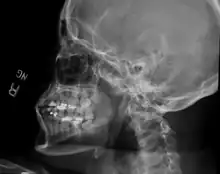

| Sagittal section of the articulation of the mandible. | |

The joint involved with jaw dislocation is the temporomandibular joint (TMJ). This joint is located where the mandibular condyles and the temporal bone meet.[4][6] Membranes that surround the bones help during the hinging and gliding of jaw movement. For the mouth to close it requires the following muscles: the masseter, temporalis, and medial pterygoid muscle. For the jaw to open it requires the lateral pterygoid muscle.[4]